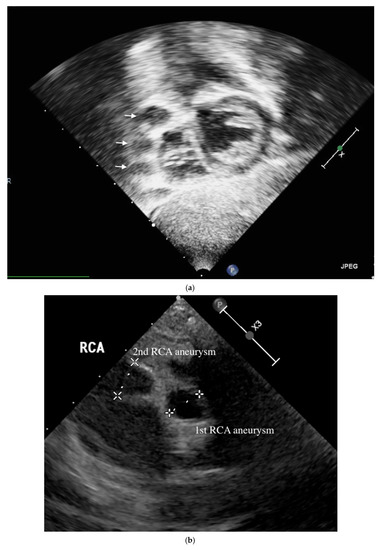

Figure 1.

Transthoracic echocardiology on the 16th months after illness of aneurysm. Three RCA aneurysms in a beaded arrangement from the subcostal view of echocardiography (a) and transthoracic echocardiogram imaging showed first with second RCA aneurysm (b) as well as first with third RCA aneurysm (c).

A 4-month-old infant girlwho presented with intermittent fever without explanation for 14 days was admitted.Laboratorydata revealed leukocytosis (19.5 × 109/L), high sensitivityC-reactive protein (CRP, 1139.04 nmol/L), and thrombocytosis (590 × 109/L). Negative culture reports were found in blood and urine. The empirical antibiotics administration did not achieve clinical improvement. The subcostal view of echocardiography andtransthoracic echocardiography (TTE) revealed three giant fusiform aneurysms of the proximal right coronary artery, along with other smaller aneurysms in the left coronary system. (Figure 1) Acute mitral insufficiency with moderate pericardial effusion was also present. The three beaded aneurysms were subsequently confirmed on a selective right coronary angiogram. (Figure 2) The fever resolved after receivinga high-dose intravenous immunoglobulin (IVIG) infusion. Aspirin with anticoagulant drugs (subcutaneous injection of low molecular weight heparin) administration was initiated and serial echocardiography as well as invasive coronary angiography follow-up were regularly performed sincethe giant aneurysm’s detection. (Figure 3) This report revealeda “beaded aneurysm” as a special medical image for KD.Itsfundamental nature of non-contiguous aneurysms could be a key to identifying antecedent KD vasculopathy compared toother coronary artery aneurysms. Written informed consent was obtained from the participant for the publication of this case report.

A pediatrician must check the echocardiography imaging of coronary arteries in infants with prolonged fever and evidence of elevated inflammation markers whenever the reasonable cause is absent because positive echocardiography findings were regarded as a set standard for acute KD accordingly. Coronary aneurysms can occur in up to 25% of KD children without a timely infusion of high-dose IVIG such as in this index case.As coronary aneurysms have become rare due to the widespread use of IVIG therapy for KD, beaded aneurysm is considered to be even rarer. There are no reports on the frequency of beaded aneurysms in KD, but it is presumed to be relatively rare.The final size of coronary aneurysms defines the future risk stratification generally speaking. In small or medium-sized aneurysms (<8mm or Z score <10), spontaneous regression of the aneurysms without significant cardiovascular sequela such as long-term luminal myofibroblastic proliferation is possible. In this case, the subcostal view of echocardiography and TTE revealed three giant fusiform aneurysms of the proximal right coronary artery, along with other smaller aneurysms in the left coronary system (Figure 1a–c). The three beaded aneurysms were confirmed by coronary angiogram is showed in Figure 2. In contrast with smaller aneurysms, giant aneurysms (>8 mm or Z score >10) seldom or never regress over time, which could be observed from the timeline of the index case(Figure 3).